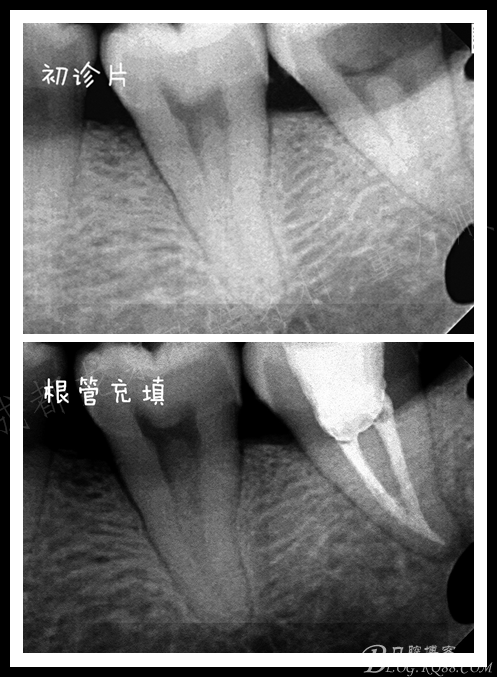

龋坏面积非常大 患者是在日本留学的时候做的治疗,由于当时没有及时的复诊导致现在的情况 ,患牙有明显的自发痛症状,阵发性钝痛。

超声器械对远中稍加施力即可看到根管口,8号挫探查根管虽说阻力很大,但还是有下去的趋势。

复诊非常准时 ,超声配合牙片 定位根管的大致走向,一点一点的往下走,很快 近舌根管口找到了,8号挫慢慢平衡立法下至中段。窃喜

近中 由于个人操作问题 差点搞个人造根管出来,近颊根是耗时最久的 还好后来没有造成更严重的后果,期间配合超声荡洗,行根管预备 充填

复查虽然术后反应消失了,但是 根管并没有做到标准的工作长度。相信我,我真的已经尽力了。